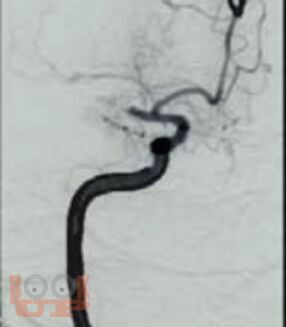

Руководство стандартизирует подходы к диагностике, лечению, реабилитации и вторичной профилактике ишемического инсульта. Изложение построено в соответствии с реальной логикой ведения пациента: от дефиниций и дифференциальной диагностики с имитаторами, через патогенетические подтипы, экстренную нейровизуализацию, реперфузионную и базисную терапию, раннюю реабилитацию, до поиска причины инсульта и вторичной профилактики.

Материал представлен в компактной форме с использованием схем, таблиц, алгоритмов и клинических примеров. Отдельные разделы посвящены инсульту у беременных и церебральному венозному тромбозу.